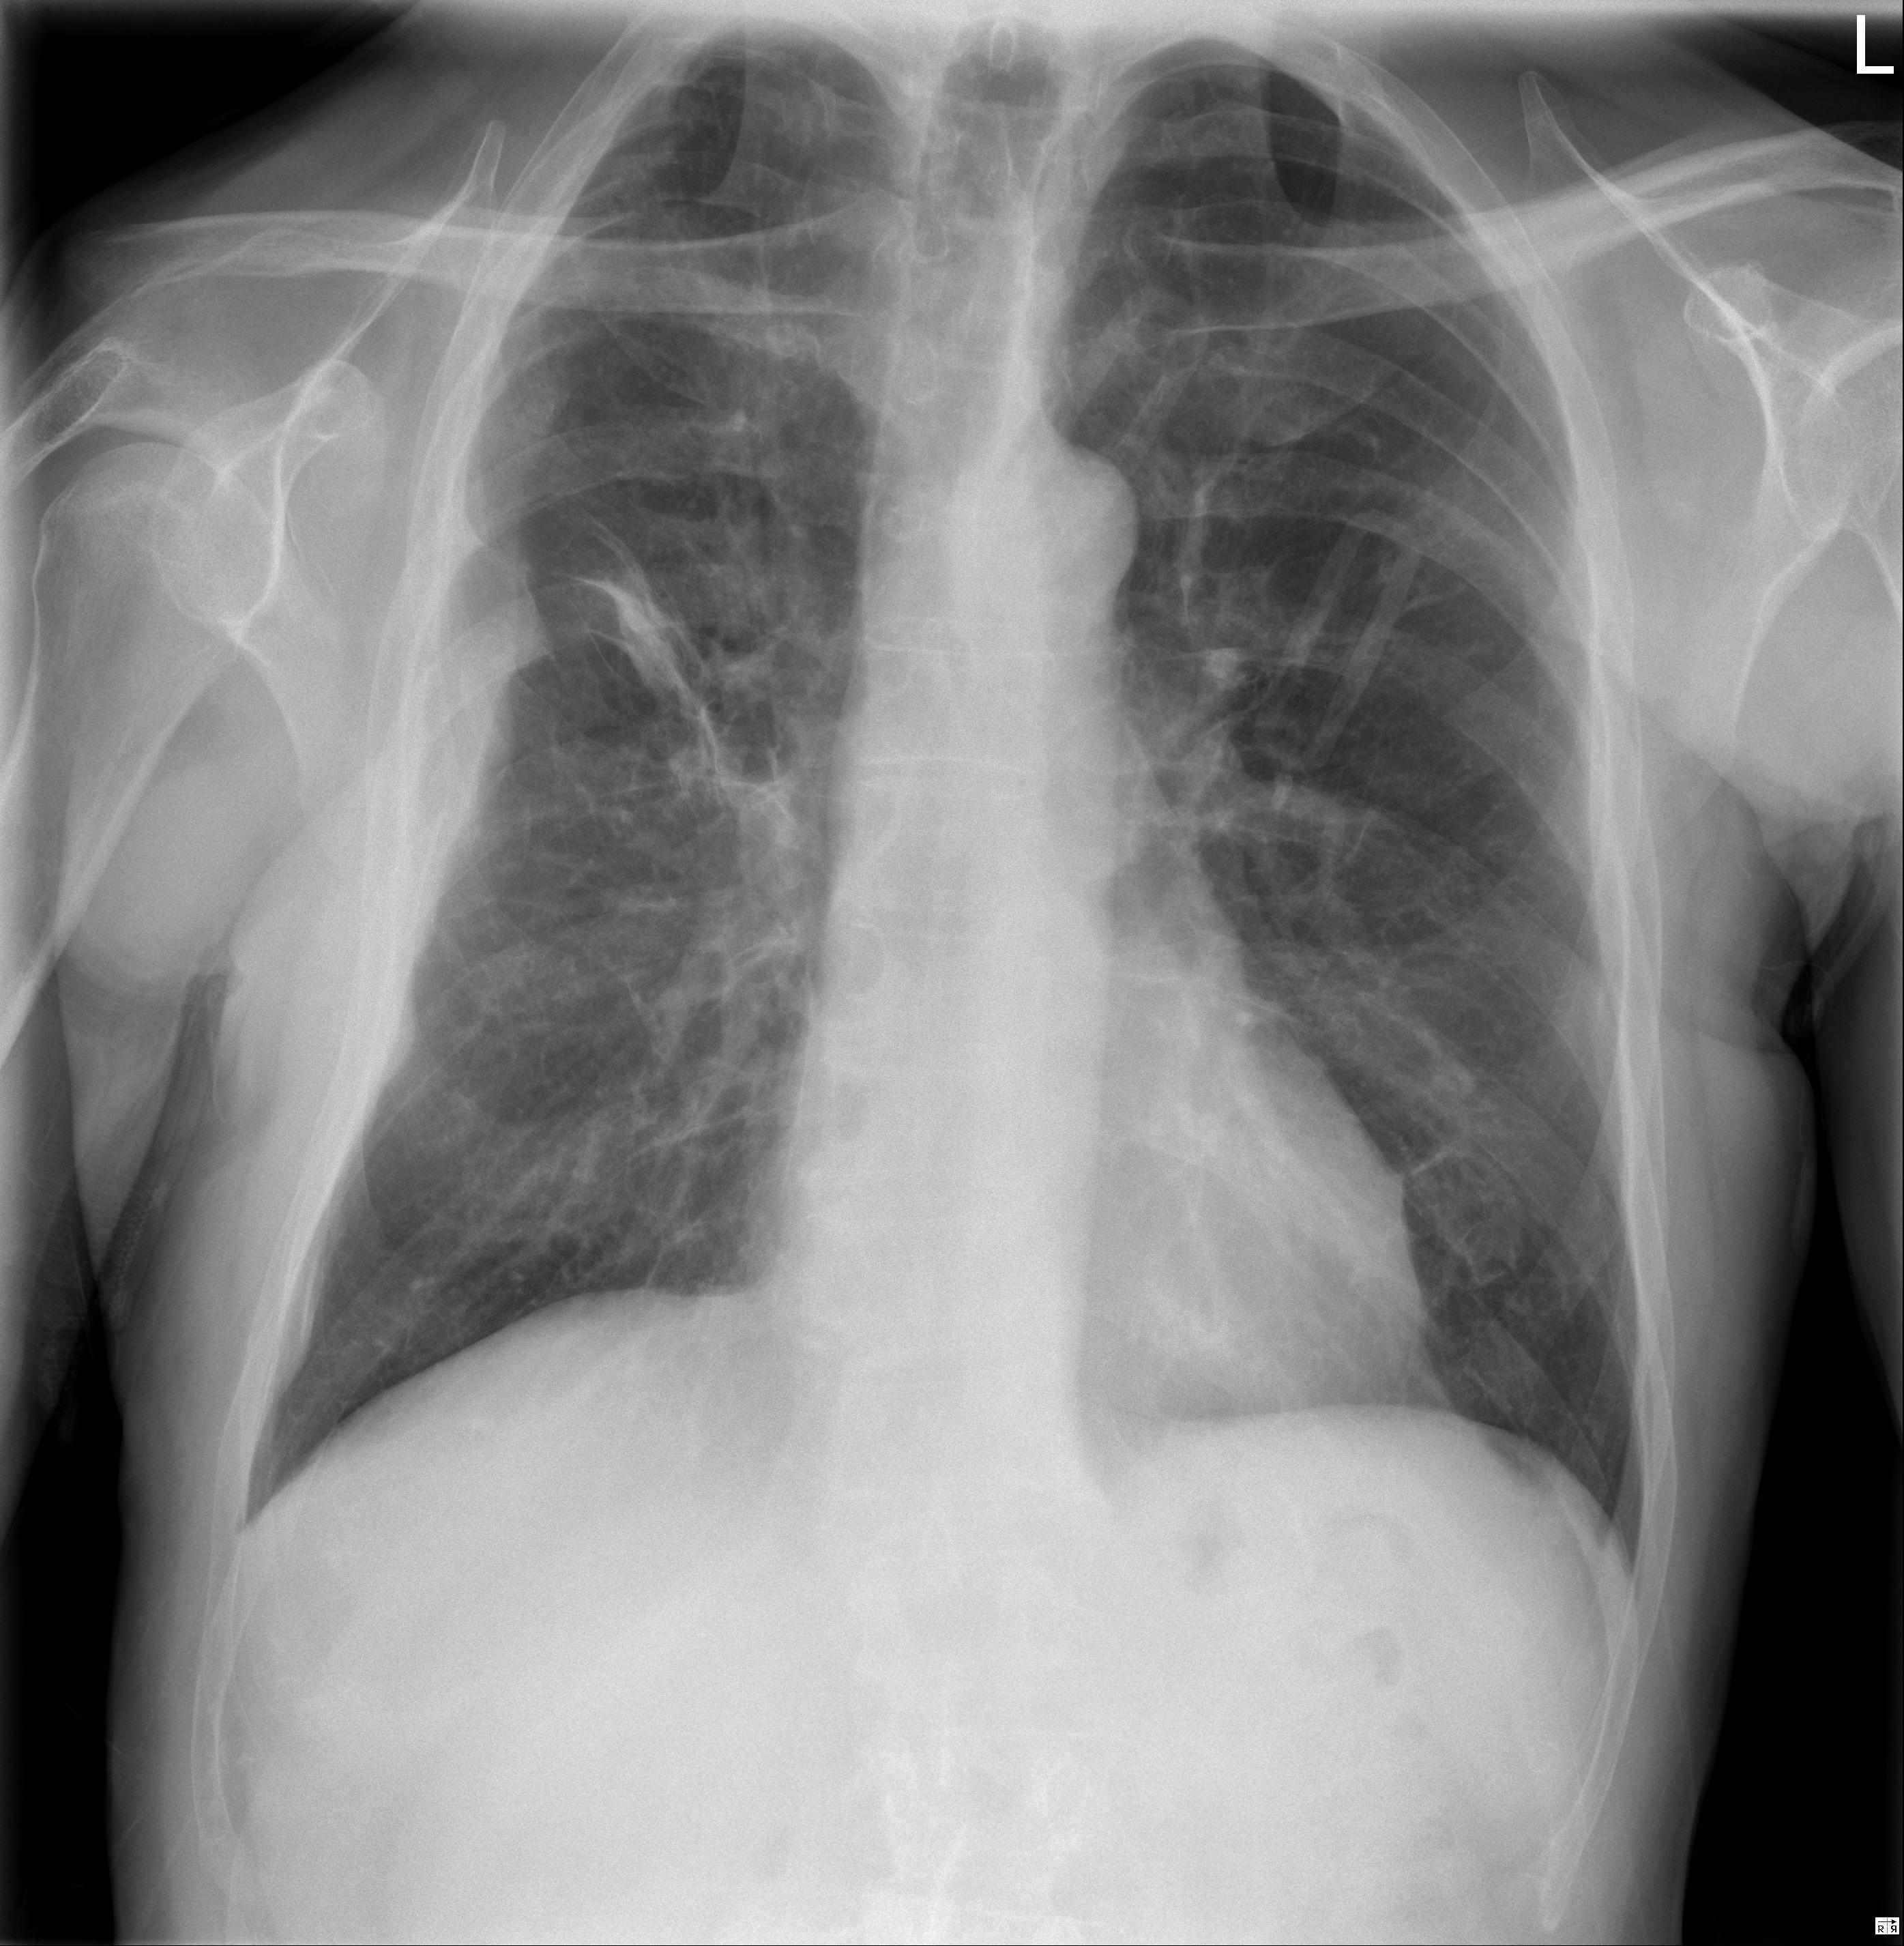

1 Tórax